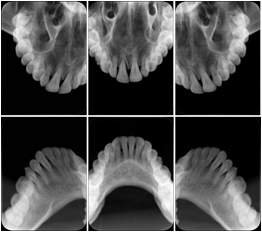

2. A patient requests cosmetic surgery to enhance their facial appearance. The case requires consultation between an orthodontist in New York and an oral surgeon in California. The cephalometric series of 2D projections constructed from a volumetric CT data set that is used for the discussion is arranged by a Structured Display for transfer between the two practitioners.

Cephalometric Series Structured Display

Figure OO-2. Cephalometric Series Structured Display

3. A dental provider wishes to capture a series of DICOM IO images for the patient’s dentition. The tooth morphology, teeth are divided into molars, premolars, canines and incisors, and a number of images for each jaw. The anatomic information was captured utilizing the triplet of schema. This standard code sequence is based on ISO 3950-2010, Dentistry - Designation system for teeth and areas of the oral cavity.

Every IO image should have anatomic information either through the primary or modifier sequence.

In most standard cases, images are oriented in structured layouts. These structured displays are useful to be shared between providers for reference purposes.

Table OO.1.1-1 shows structured display standard templates, where Viewset ID is based on the Japanese Society for Oral and Maxillofacial Radiology (JSOMR) classification provided by JIRA (Japan Medical Imaging and Radiological Systems Industries Association, www.jira-net.or.jp). Expected or typical teeth to be imaged location, region and designation codes are based on ISO 3950-2010, Dentistry - Designation system for teeth and areas of the oral cavity. For all the hanging protocols listed in OO.1.1-1, the value to use for Hanging Protocol Creator (0072,0008) is "JSOMR" and the value to use for Hanging Protocol Name (0072,0002) does not include "JSOMR" (e.g., "DL-S001A", not "JSOMR DL-S001A").